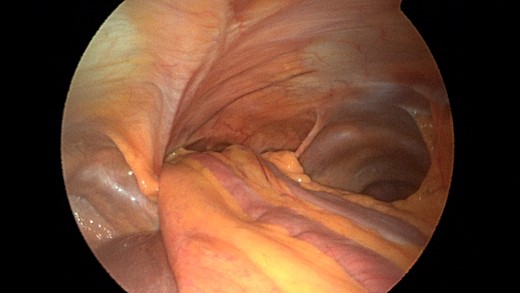

Patient underwent a laparoscopic approach in lithotomy positioning with the primary surgeon working between the legs. Three working ports were used, a 12 mm port at the umbilicus and two 5 mm ports; one in the LUQ and one in the RUQ. Upon initial laparoscopy multiple loops of small bowel were progressively reduced out of the hernia sac which also included the ascending colon and part of the transverse colon (Figs 3 and 4). All the small bowel and the colon appeared viable. The redundant parietal peritoneal hernia sac was excised out of the right inferior hemithorax utilizing a LigaSure (Covidien) (Fig. 5). The falciform ligament was also taken down all the way to the diaphragm. The defect in the diaphragm measured to be approximately 9 cm by 4 cm. A section of Pariatex composite mesh was then trimmed to 2 cm in width by 9 cm in length. Three stay sutures of 0 Ethibond were placed laterally and in the middle of the mesh. This was placed into the peritoneal cavity after soaking it in vancomycin with local anesthetic. The sutures were then percutaneously brought through the diaphragm edge that was unattached to the anterior abdominal wall and then subsequently through the anterior abdominal wall. These were then tied thereby re-approximating the unattached edge of the diaphragm to the anterior abdominal wall near the xiphoid (Fig. 6). Additional 0 Ethibond sutures were placed in between these initial ones percutaneously with a suture passer.

Closer view of the retroxyphoid defect demonstrating its large size with the edge of the diaphragm unattached to the undersurface of the abdominal wall.